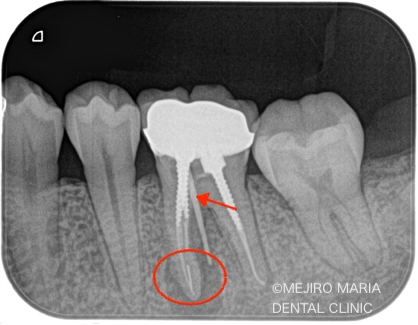

根管治療を2回施し、2回目の治療では、術前に確認されていた瘻孔は消失し、すでに治癒傾向を示していました。

術後3ヶ月で、根尖部に確認されていた黒い透過像(根尖性歯周炎)は明らかな縮小傾向を示していたため、最終補綴(被せ物)の処置を行いました。

今後2年間の経過観察を行い、術後の予後を確認していく予定です。

今回の治療では、大きいスクリュータイプの築造体を除去し、かつ根尖にある破折ファイルを除去したが、レントゲンで分かるのは、健全な歯質をほとんど削らず対処できたことも、今回の症例の重要なポイントであると考えています。

なぜかというと、どんなにコンセプトを守って治療をしたとしても、大きく歯を削り過ぎてはその歯の予知性を低下させてしまうからです。また、ほとんどの再根管治療でのトラブルは、築造体の除去時に大きく削り過ぎたことで、かえって状況を悪くしてしまった症例もよく拝見します。そのため歯科医院を選ぶ際には、設備はもちろんのこと、熟練した技術を伴った歯科医師を選択することを推奨します。